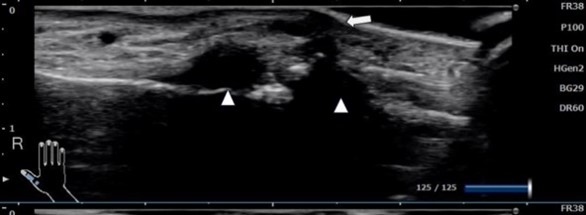

A. 必ずエコー検査をしてもらってください。

どちらも指背側に出来た軟部腫瘍ですが、エコー所見では左は充実性腫瘍(エコーで内部が充填されている)右は黒い部分がありのう胞性の変化があります。左は他医で穿刺されて何も出ないということで紹介されていらっしゃいました。痛いだけ損です。

田中利和著『クリニックで診る手 鑑別診断から治療まで』医事新報社より借用